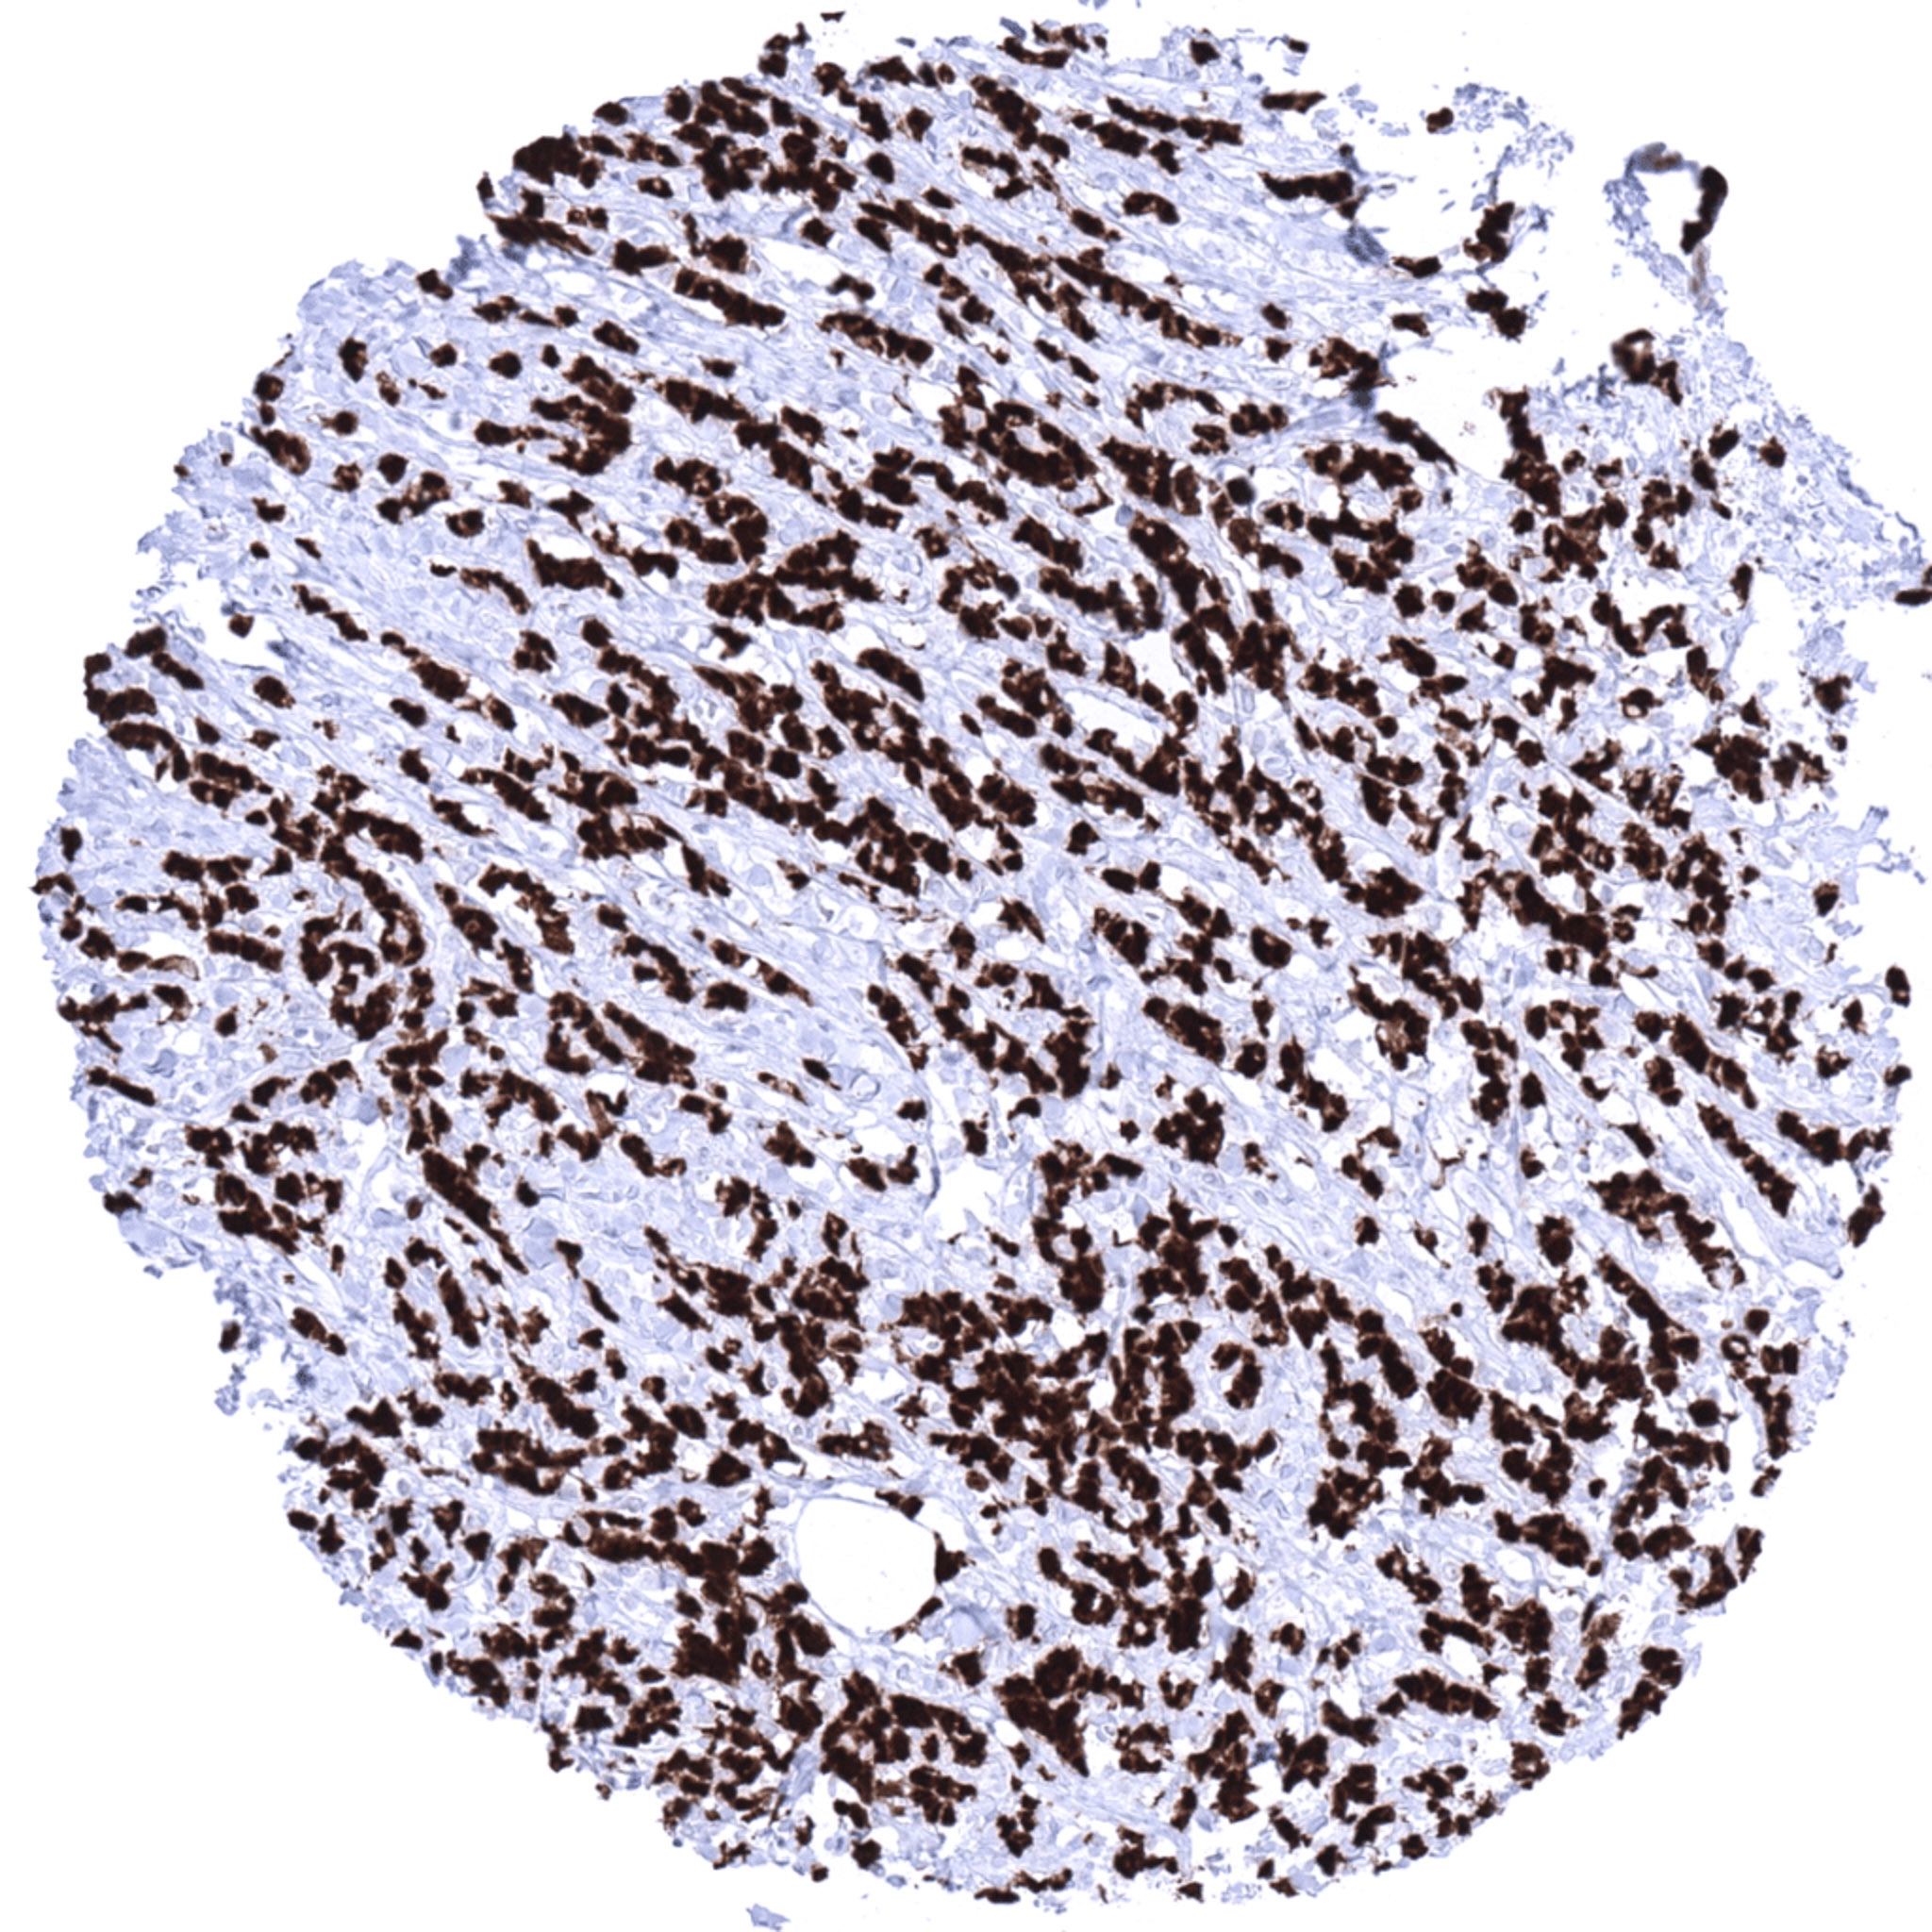

Pancreas- Ductal adenocarcinoma with strong S100P immunostaining of tumor cells. Few S100P positive granulocytes are also seen.